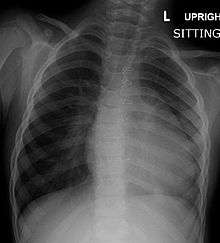

Before more sophisticated techniques became available, chest x-ray was the definitive method of diagnosis. The abnormal "coeur-en-sabot" (boot-like) appearance of a heart with tetralogy of Fallot is classically visible via chest x-ray, although most infants with tetralogy may not show this finding.[21] Absence of interstitial lung markings secondary to pulmonary oligaemia are another classic finding in tetralogy,[22] as is the pulmonary bay sign.

| Right ventricular hypertrophy | The right ventricle is more muscular than normal, causing a characteristic boot-shaped (coeur-en-sabot) appearance as seen by chest X-ray. Due to the misarrangement of the external ventricular septum, the right ventricular wall increases in size to deal with the increased obstruction to the right outflow tract. This feature is now generally agreed to be a secondary anomaly, as the level of hypertrophy tends to increase with age.[18] |